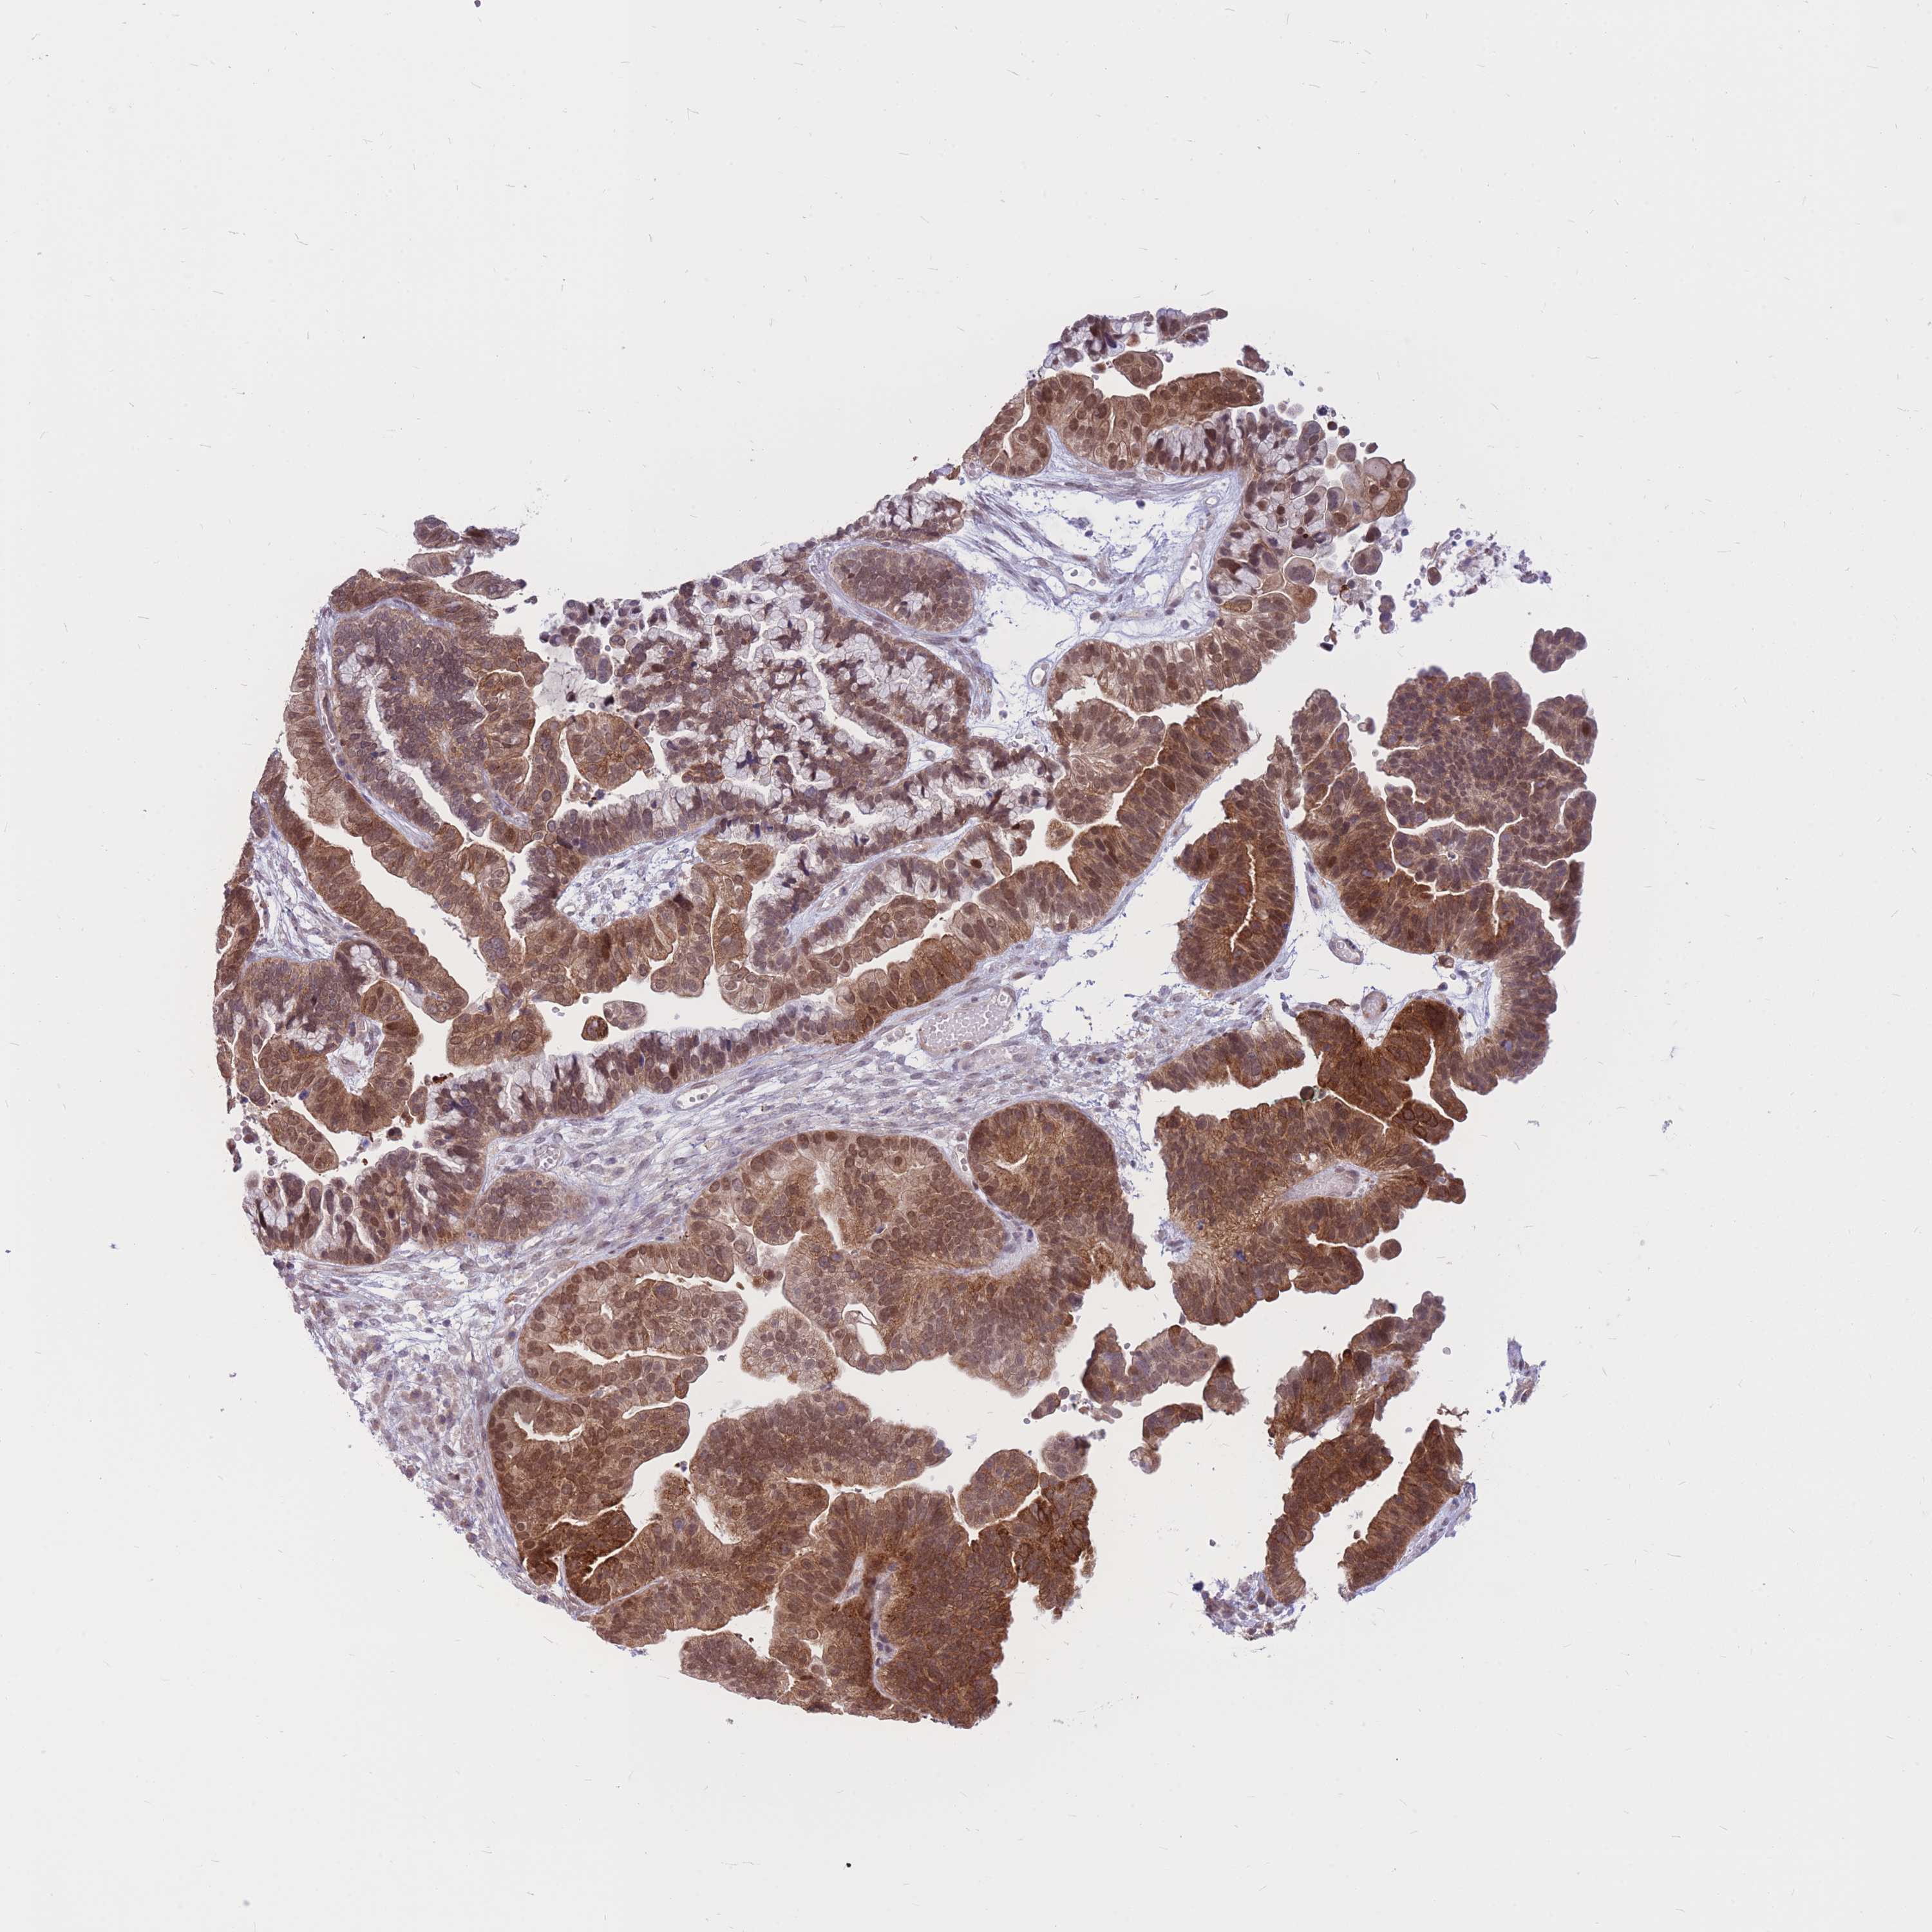

OVARIAN CANCER - Protein expressioni

A mouse-over function shows sample information and annotation data. Click on an image to view it in a full screen mode. Samples can be filtered based on level of antibody staining by selecting one or several of the following categories: high, medium, low and not detected. The assay and annotation is described here.

Note that samples used for immunohistochemistry by the Human Protein Atlas do not correspond to samples in the TCGA dataset.

Antibody stainingi

Antibody staining in the annotated cell types in the current human tissue is reported as not detected, low, medium, or high, based on conventional immunohistochemistry profiling in selected tissues. This score is based on the combination of the staining intensity and fraction of stained cells.

Each image is clickable and will lead to virtual microscopy that enables deeper exploration of all samples and also displays staining intensity scores, fraction scores and subcellular localization as well as patient and tissue information for each sample.

Antibody HPA036786

Antibody CAB017849

Staining

High

Medium

Low

Not detected

Intensity

Strong

Moderate

Weak

Negative

Quantity

>75%

75%-25%

<25%

None

Location

Nuclear

Cytoplasmic/membranous

Cytoplasmic/membranous,nuclear

Cystadenocarcinoma, serous, NOS

Carcinoma, endometroid

Cystadenocarcinoma, mucinous, NOS

Carcinoma, NOS